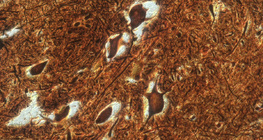

100x magnification